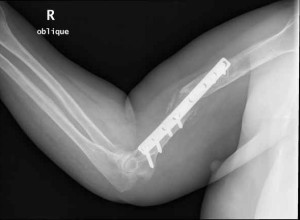

Применение титановых пластин при травмах верхних конечностей. Как правило это тыльная поверхность руки. В отличии от передней поверхности, где сосредоточены нервные окончания, мышцы и сосуды, которые можно повредить, на тыльной стороне кости размещены ближе к поверхности кожи. Это дает возможность применять установку титановой пластинки. Поскольку на передней поверхности и ладони большое количество мышц, сосудов и нервных окончаний, которые могут быть повреждены, то здесь их не ставят. А вот на тыльной стороне руки кости находятся ближе к поверхности кожи, потому возможность применения титана здесь есть.

Если пострадали локтевой, лучезапястный или плечевой сустав, используются специальные фиксаторы, пластины или анкеры, с помощью которых травмированный связки крепятся к костным образованиям. Установленная в руке пластина через год может быть удалена. Перед удалением следует убедиться в наличии костной мозоли. Титановые фиксаторы также можно оставить навсегда. В случае травмы с нарушением целостности ключицы применяют никелевые или титановые пластины, которые имеют изогнутую форму, повторяя анатомическую кривизну кости.